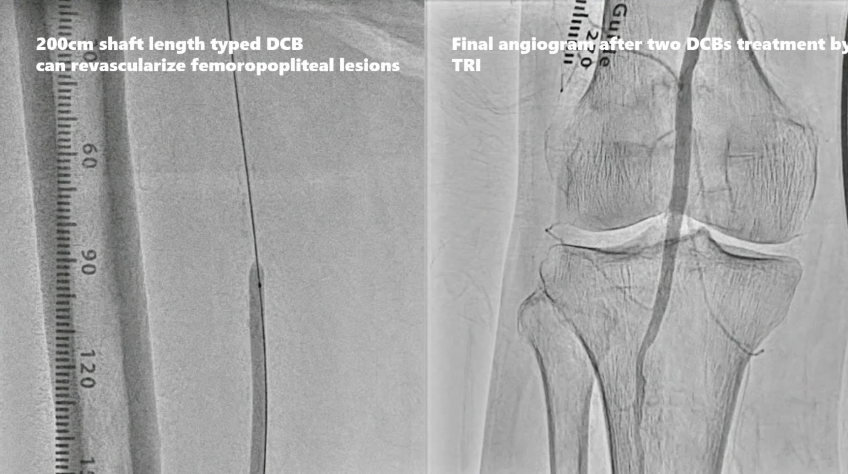

病例三:双侧髂动脉、股总动脉狭窄

经桡动脉入路,双侧髂动脉植入S.M.A.R.T. RADIANZ®支架,日本最近已上市200cm长轴药物涂层球囊(DCB),可用于TRI处理股浅动脉病变,双侧股总动脉至腘动脉近端使用DCB扩张,最终造影结果满意。

动脉长鞘怎么置入桡胜一筹丨原口拓也:经桡动脉入路在下肢动脉疾病腔内治疗中的优势——RADIANZ应用经验_https://www.jmylbn.com_新闻资讯_第35张